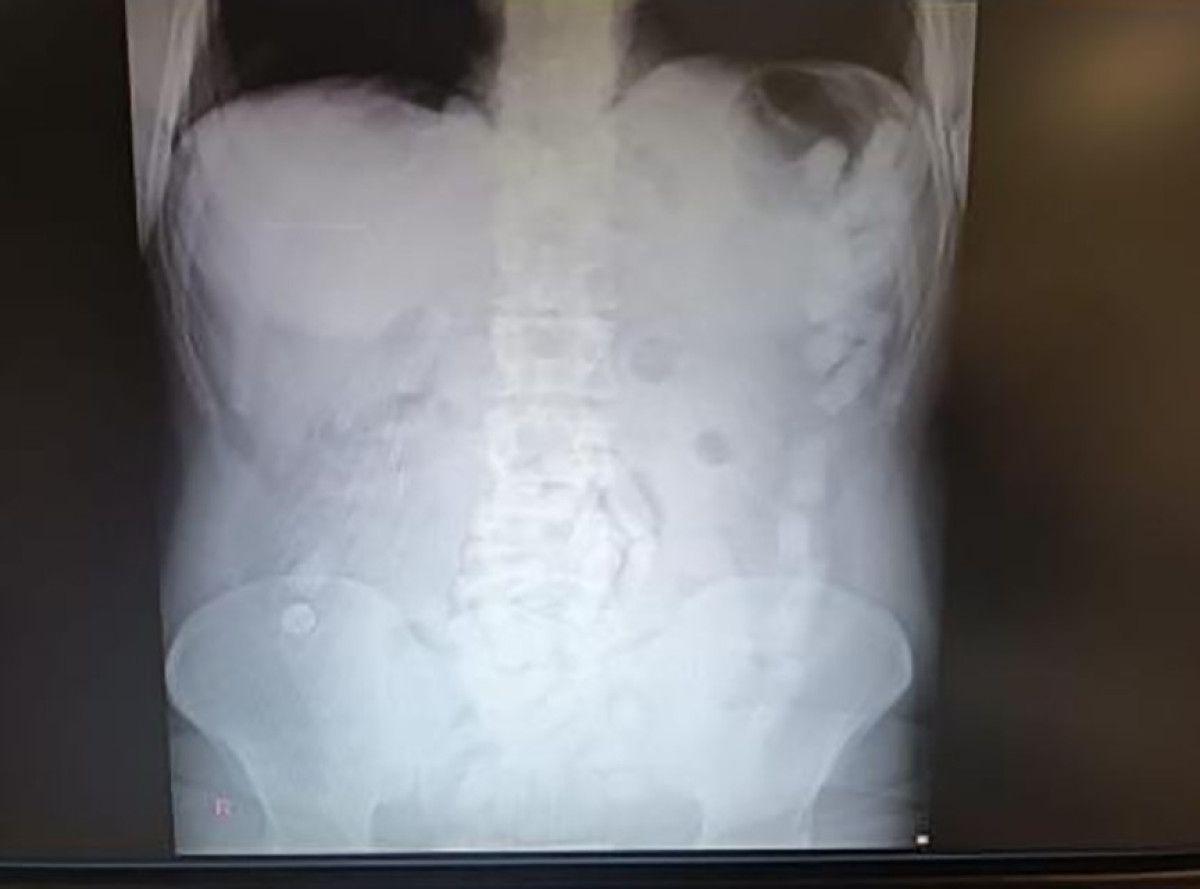

Kayseri Şehir Hastanesinde ultrason çekimi ile yapılan denetimde şahsın midesinde çok sayıda kapsül olduğu tespit edildi.

Yapılan operasyonla şahsın midesinden çıkarılan 100 adet kapsülün içerisinde 729 gram uyuşturucu unsur ele geçirildi.